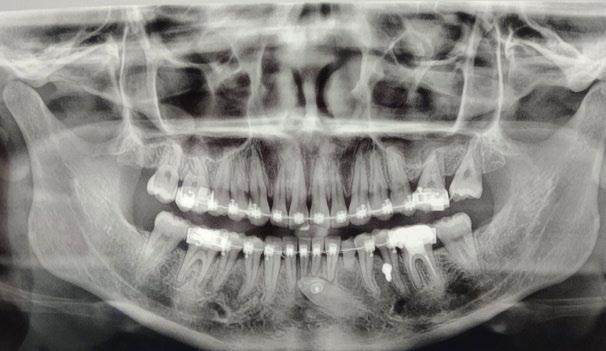

Se presenta un paciente de 18 años de edad que refiere tener hemofilia tipo A, moderado grado V. En los estudios de inicio extraorales, se observa en la Figura 1 el frente, sonrisa y perfil. En la radiografía lateral de inicio (Figura 2) se evidencian el overjet y overbite reducidos, clase I esquelética, hiperdivergencia y biprotrusión dentoalveolar.

En la radiografía panorámica (Figura 3) se observan las raíces cortas de los incisivos centrales y del O.D. 22, además de los terceros molares superiores e inferiores en formación.

Figura 3. Radiografía Panorámica inicio.